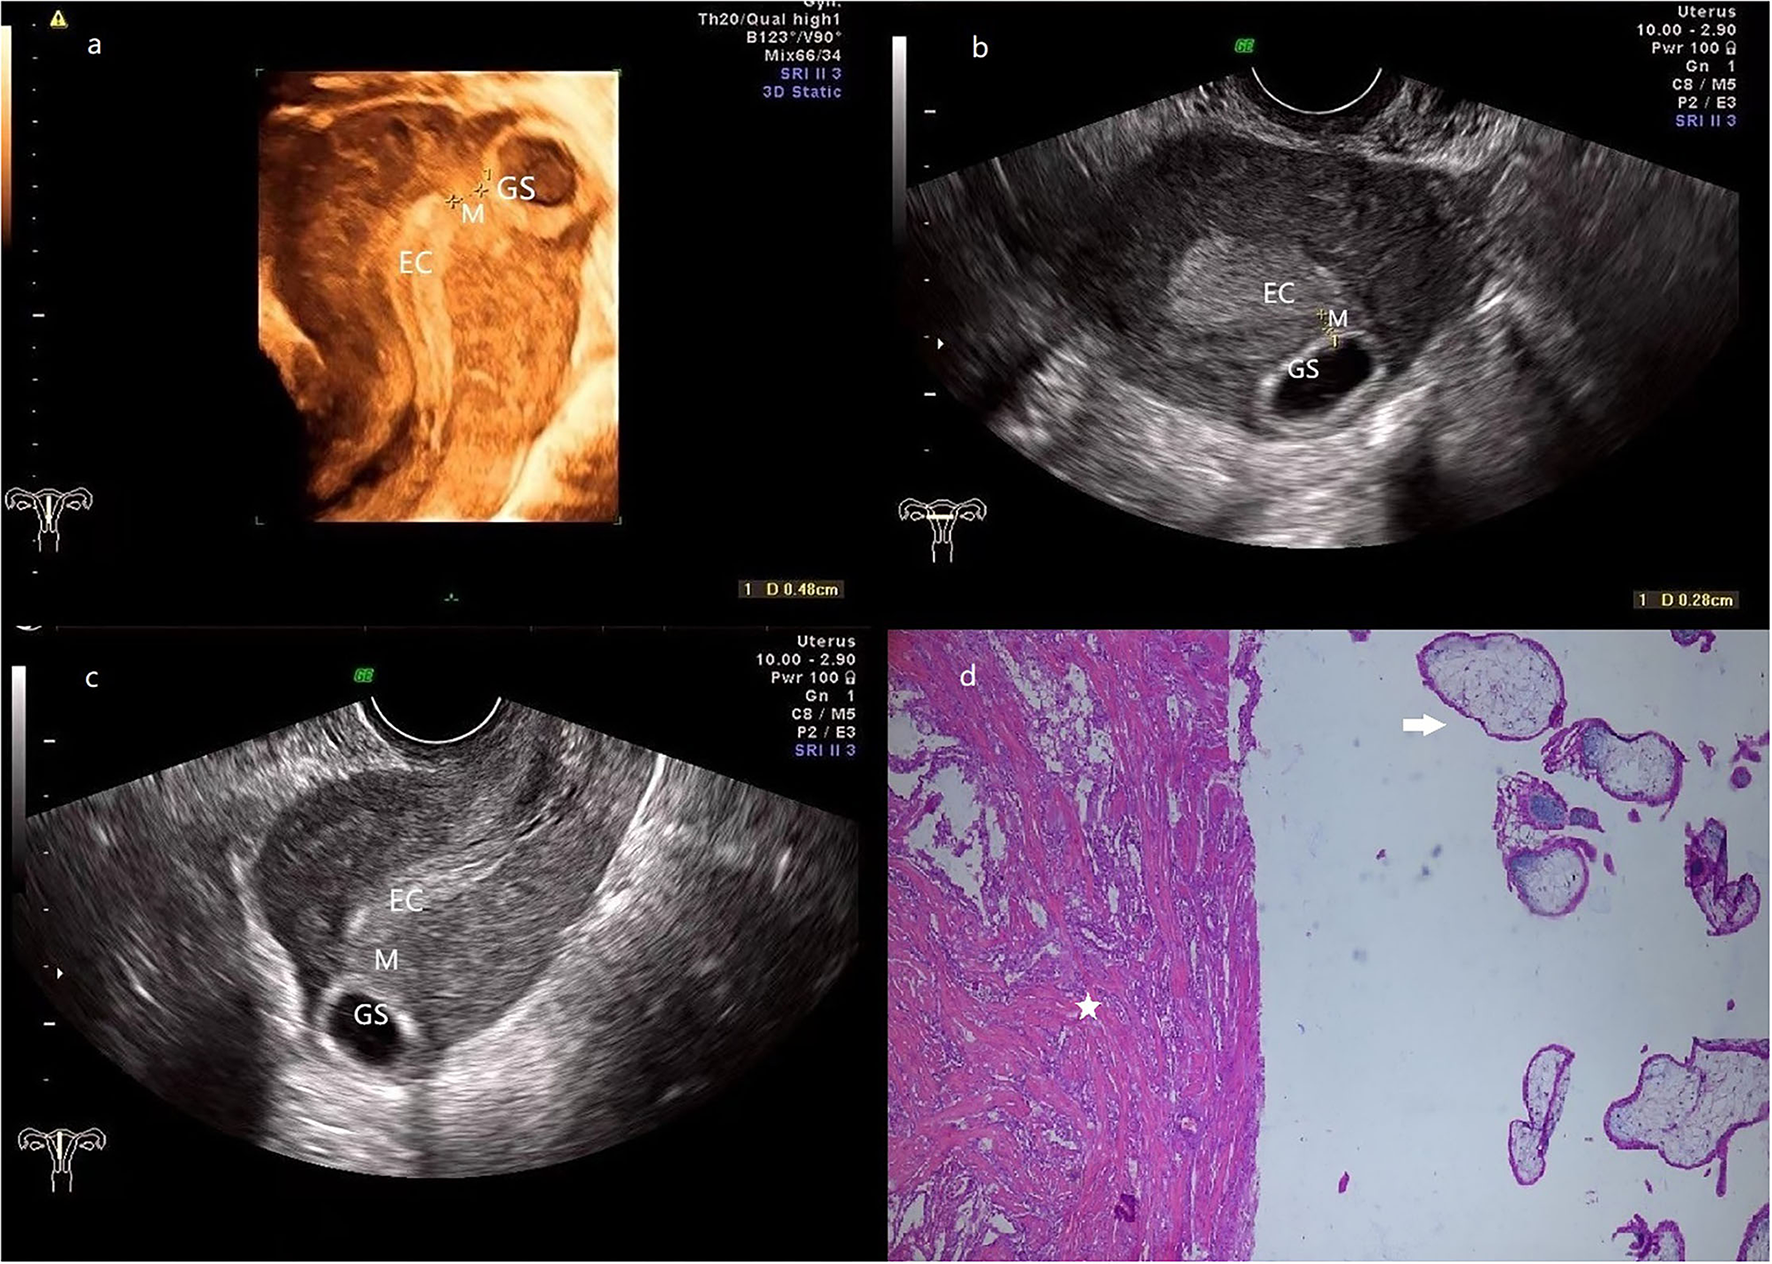

Figure 2

(a) 3-D ultrasonography reveals the relative location of EC, GS (a size of 2.7*1.0 cm), and the myometrium (0.5 cm in thickness) is located between them. (b,c) transversal (b) and sagittal (c) section image showed that the GS is located at the left posterior wall of the fundus, and the connection with EC is disrupted by the myometrium. (d) The pathologic examination demonstrates that muscular tissue (star) coexists with the chorionic villus (arrow). (Patient 2, GS, gestational sac; M, myometrium; EC, endometrial cavity).